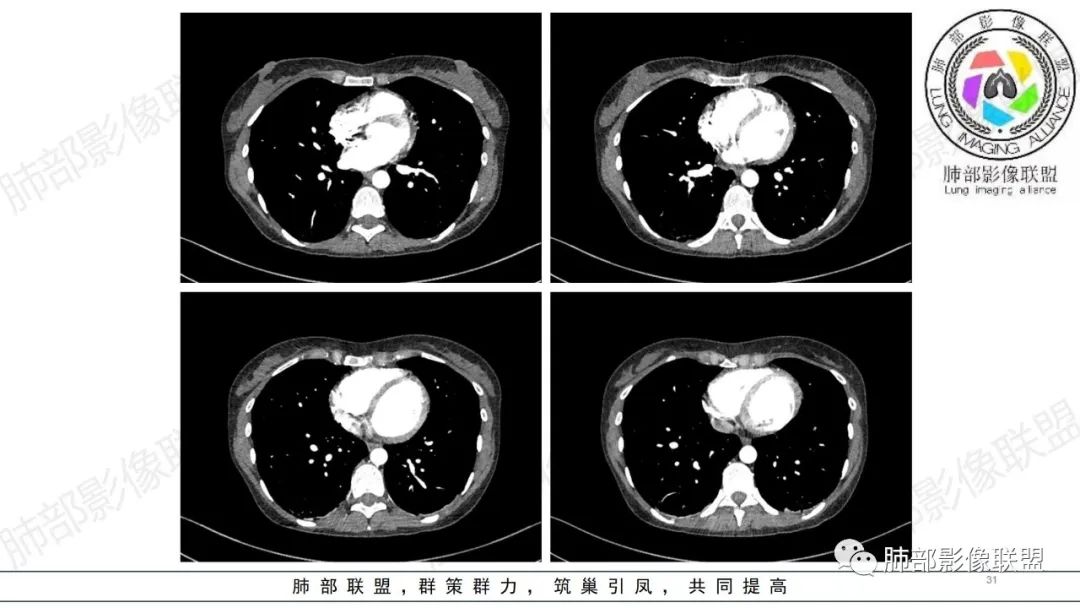

【病例】肺部弥漫大B淋巴瘤病例思考及启示

34岁女性患者,“哮喘”病史30年,近期有可疑刺激性气体吸入史;因乏力半年,咳嗽、憋气、发热4天就诊;6.1CT提示双肺广泛毛玻璃影及粟粒样结节,胸膜下闲置及血管周闲置,可见树丫征,部分小叶间隔增厚。考虑:1.过敏性肺泡炎,有可疑刺激气体接触史,胸膜下闲置,广泛毛玻璃影,地图样分布,粟粒结节边界模糊,支持过敏性肺泡炎,但糖皮激素治疗效果不佳,且动态复查血常规血红蛋白进行性降低,过敏性肺泡炎 不符合;2.肺含铁血黄素沉积症:患者30“哮喘”病史,可能为肺含铁症状,肺部CT提示双肺弥漫毛玻璃影及粟粒结节影,中下肺明显,肺底部分小叶间隔增厚,近期咳嗽、憋气、发热,血常规血红蛋白进行性下降,考虑肺含铁急性期症状,但临床无咯血症状,肺含铁不典型。综合考虑:肺含铁血黄素沉积症>过敏性肺泡炎。

肺内气腔磨玻璃结节,肝脾肿大,治疗后间质改变,弥漫大B可能